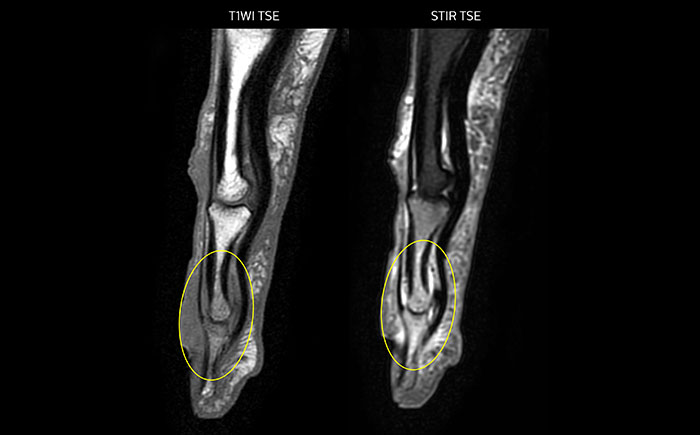

MRI examination on Prodiva 1.5T of a 72-year-old female with a malignant melanoma in the ankle. mDIXON TSE provides excellent fat suppression, without the distortion that is often seen at such extremities.